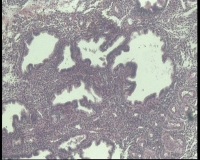

| 图片: | |

- 急!请老师看看34岁子宫内膜

| 性别 | 女 | 年龄 | 34岁 | 临床诊断 | 子宫内膜息肉? |

| 一般病史 | 末次月经:11月20日,近两个月无诱因性生活有阴道少许血性分泌物 | ||||

| 标本名称 | 宫内容物 | ||||

| 大体所见 | 膜样碎组织3.0厘米 | ||||